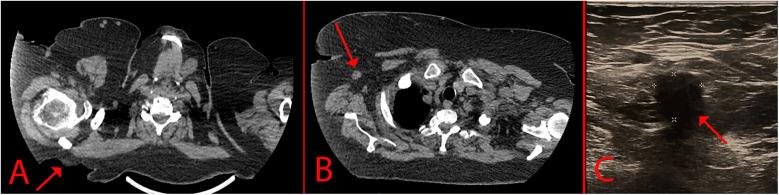

Basal cell carcinoma (BCC) is a malignant neoplasm of the skin that originates from the cells of the basal layer of the epidermis and is the most common skin cancer worldwide, accounting for more than 75% of all nonmelanoma skin cancers. About 4 million BCCs are diagnosed annually worldwide. Despite being the most common skin tumor, metastasis is rare and occurs in 0.0028%-0.55% of cases. In this case report, we present a rare case of giant basal cell carcinoma with metastasis to the subcutaneous fat in a 69-year-old woman.

基底细胞癌(BCC)是一种皮肤恶性肿瘤,起源于表皮基底层细胞,是全球最常见的皮肤癌,占所有非黑色素瘤皮肤癌的75%以上。全球每年约有400万例基底细胞癌被诊断出来。尽管它是最常见的皮肤肿瘤,但转移很少见,发生率为0.0028%-0.55%。在本病例报告中,我们呈现了一例69岁女性罕见的巨大基底细胞癌伴皮下脂肪转移的病例。